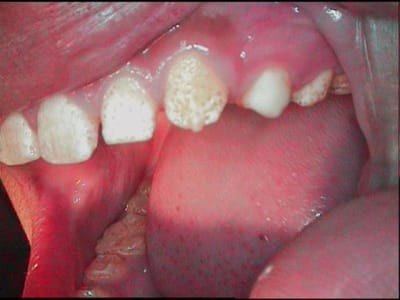

bin justement! rien en occlusal encore!!! je ne vois pas comment m'"accrocher", et j'aimerais ne pas tailler (elle est jeune encore:12ans1mois! et les 7 sont a peine émergées, les pulpes hypervolumineuses, les faces ocl quasi-plates...)

je vois bien qu'il faut faire quelque chose, mais je vois pas comment...

effectivement c'est un e amelogenese imparfaite a email pitted elle est rare c'est la fomme hypoplasique a email pitted le traitement apres conseil d'hygiene est le commpsite fluise qui comble le puit

en effet, une bonne hygiene, enseignée a l'époque des dents de lait (qui n'avaient pas d'amelogenese ) a limité le risque carieux....pour l'instant